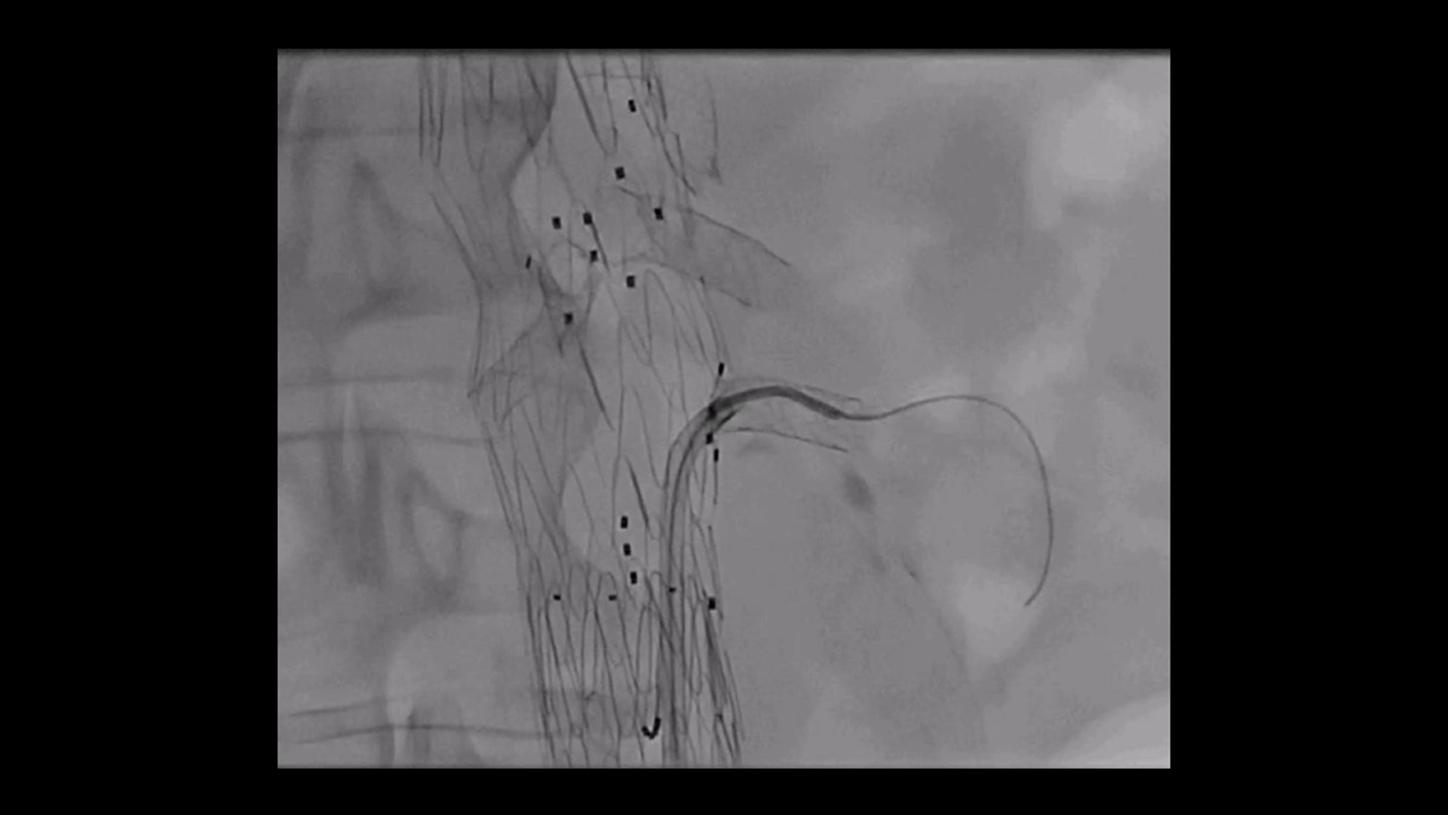

During minimally invasive procedures, it is critical to have a clear view of anatomies and devices. Yet complex imaging tasks or challenging patient conditions often impact image quality. OPTIQ AI delivers constant image quality1 defined by CNR in support of the ALARA principle, independent of patient or C-arm angulation. On top, an AI-powered algorithm reduces image noise in real time across different 2D imaging modes.

Make AI-powered imaging and clear insights your standard during interventions – with OPTIQ AI.

Future-focused IR imaging for a broad procedure mix

Discover how leading clinicians are transforming interventional radiology with Siemens Healthineers technologies. From ultra-fast 3D imaging to laser-guided needle procedures, the ARTIS icono ceiling powered by OPTIQ and syngo DynaCT are redefining what’s possible in IR. Explore real-world cases, expert insights, and the future of image-guided therapy.